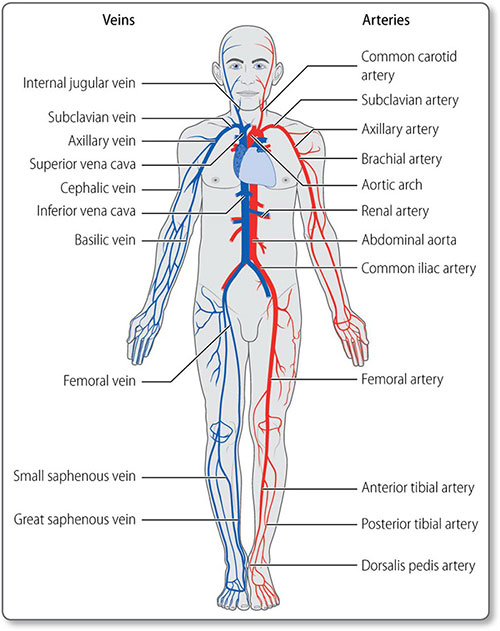

The main purpose of the cardiovascular system (Figure 1.1) is to transport substances around the body, including:

1.1 Cardiovascular anatomy